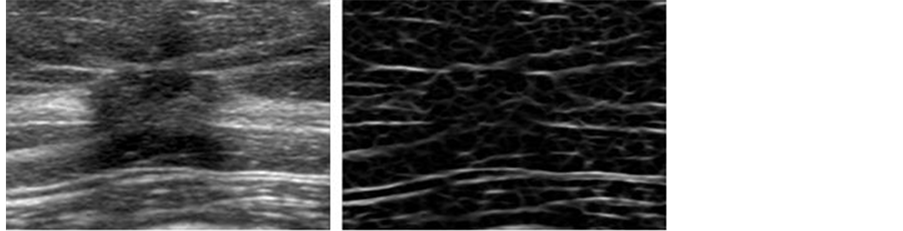

The histological classifications of these lesions were made through pathologic diagnosis. The ultrasonographic images were acquired with an ultrasound diagnostic system (APLIO XG SSA-790A, Toshiba Medical Systems Corp.) with a 12-MHz linear-array transducer (PLT-1204AT). A pixel size of each ultrasonographic image was 0.05 mm × 0.05 mm, and each image was quantized using a 256-level grey scale. Figure 1 shows an example of masses with three histological classifications. The size of these images was 20 mm × 17 mm.

Figure 1. Three masses with different histological classifications. (a) Invasive carcinoma, (b) Noninvasive carcinoma, (c) Benign.

Figure 3. Example of an image enhanced for linear structures by a filter bank. (a) Original image, (b) Enhanced image for linear structures.